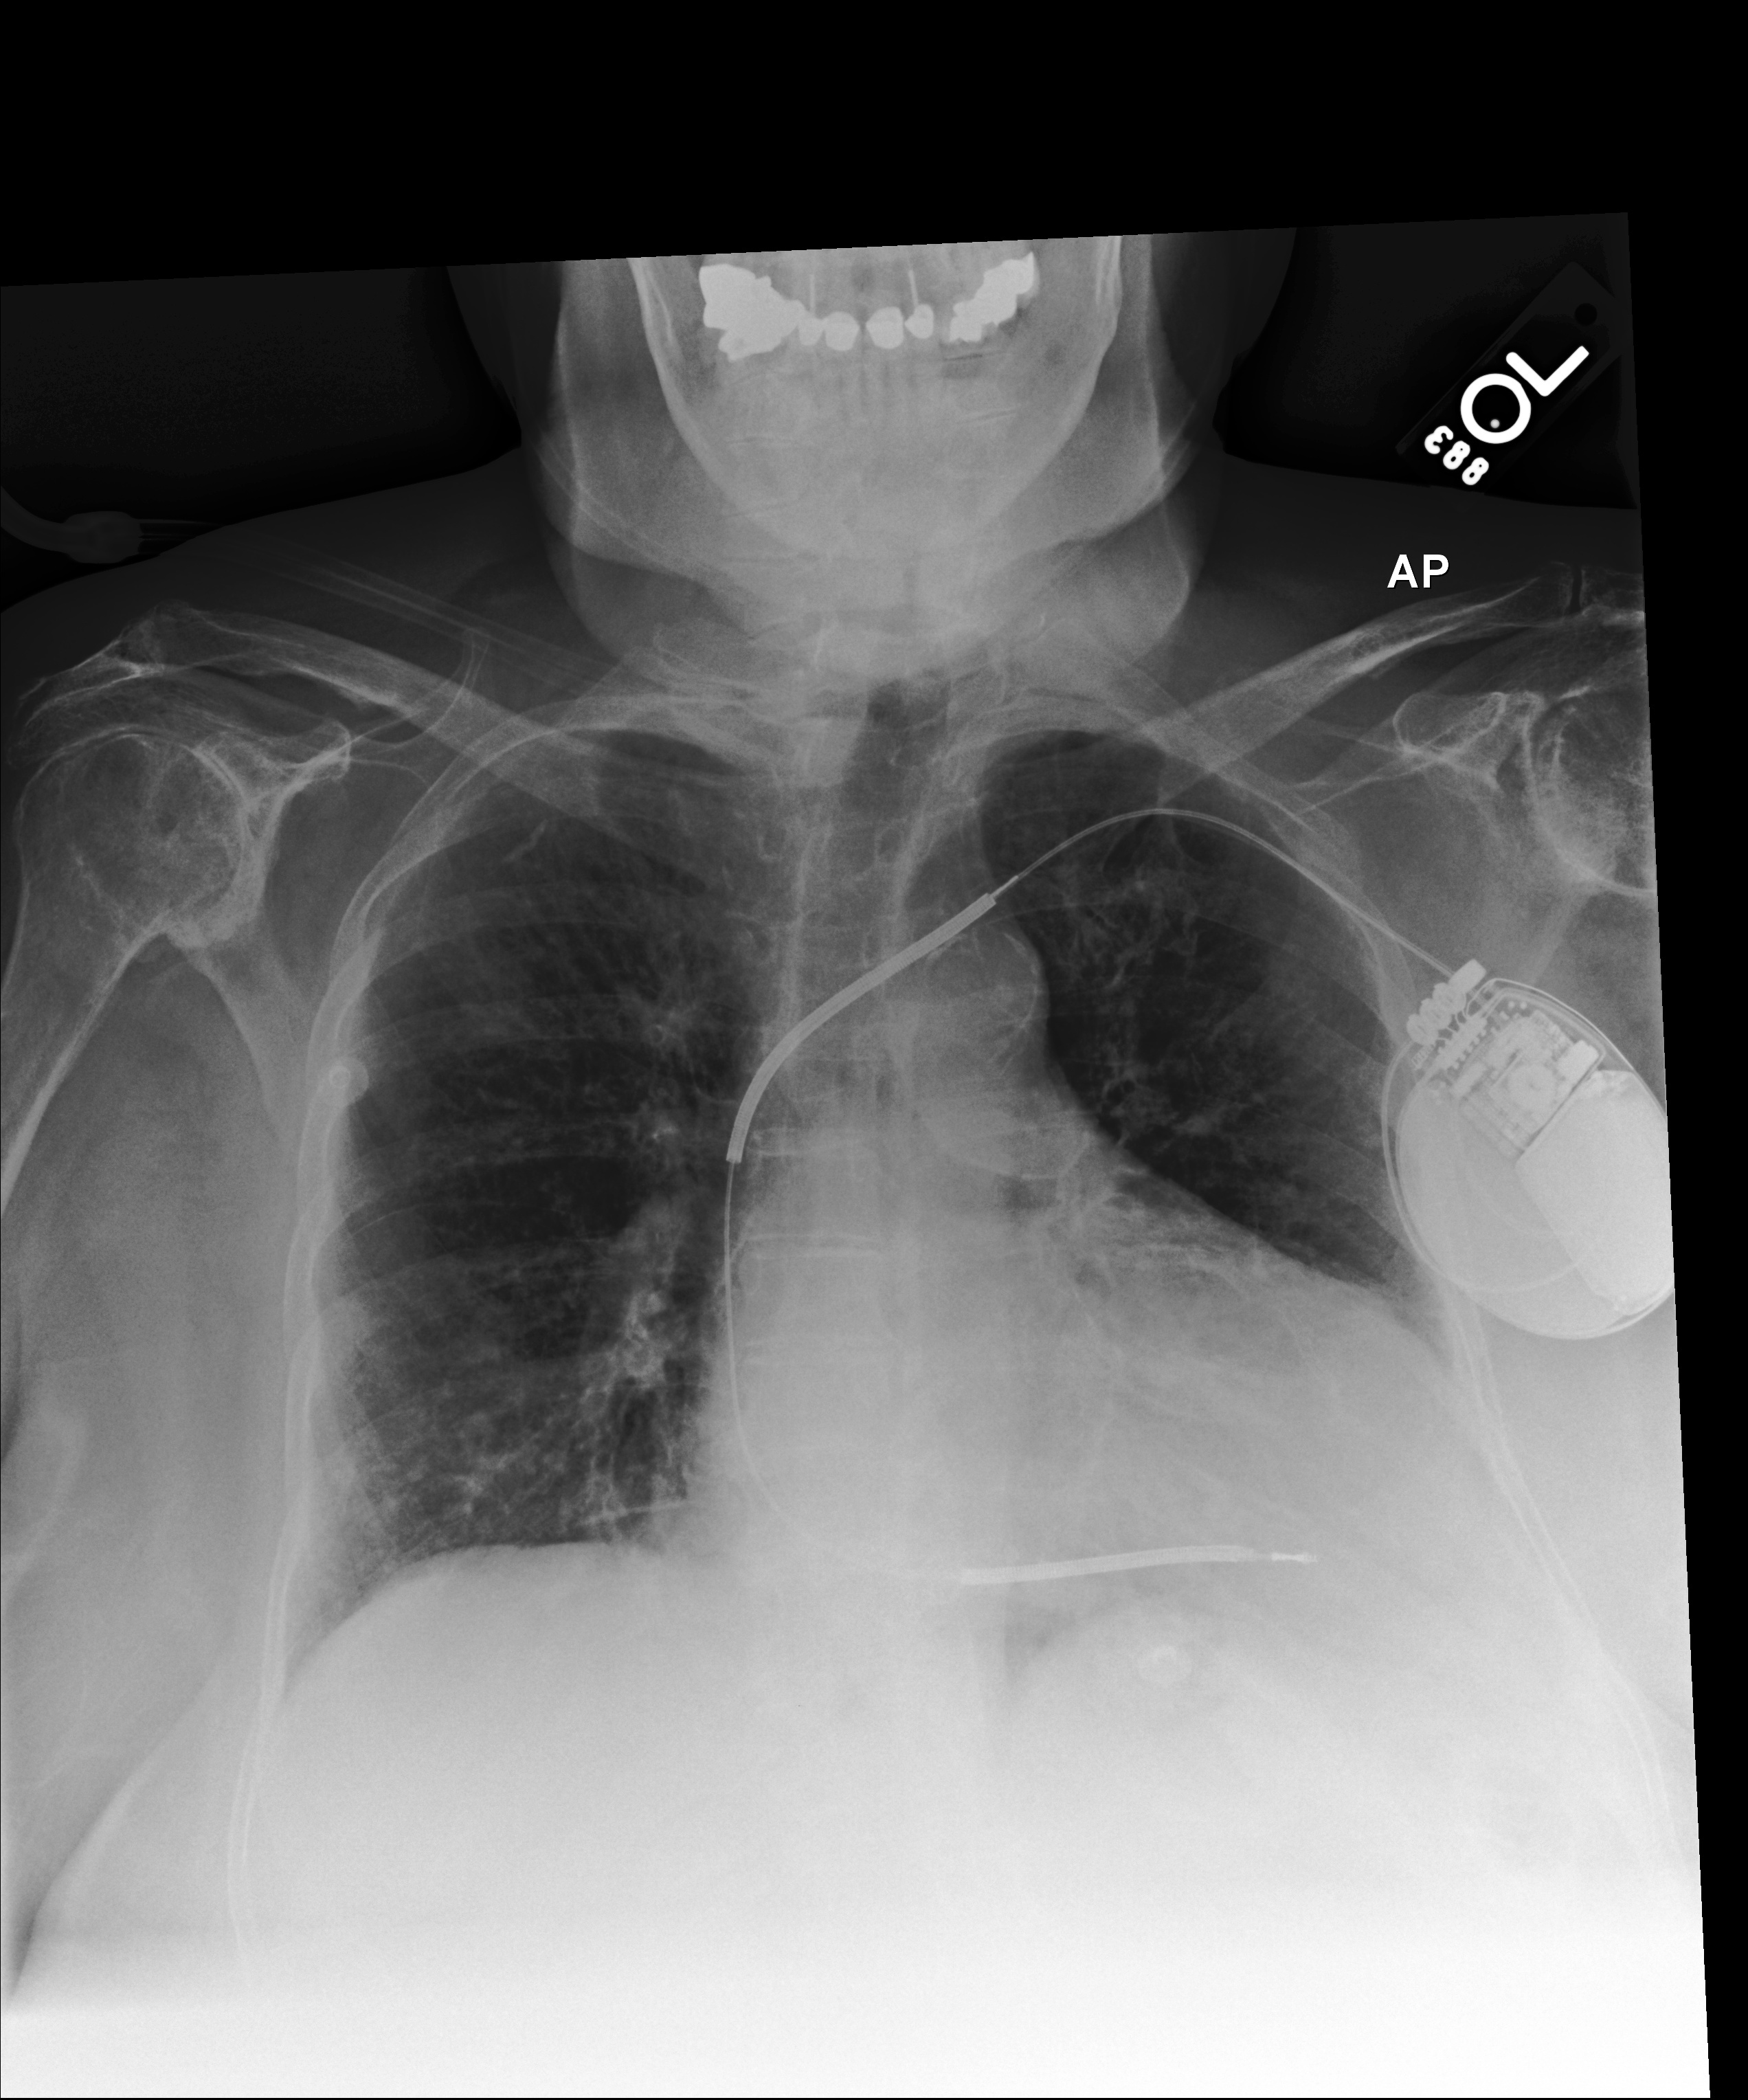

Table 4: The results of the CXR generative model using two different text prompts. The ground truth report is in the third row, and a random CXR report is in the fourth row. Feature similarity is used to calculate the generation’s similarity with the Ground Truth (GT) image.

Original Image

[Uncaptioned image] [Uncaptioned image] [Uncaptioned image] [Uncaptioned image]

Binary Image Lung Segmentation

Generated with the Original Report

[Uncaptioned image] Similarity with the GT: 88.6% [Uncaptioned image] Similarity with the GT: 85.3% [Uncaptioned image] Similarity with the GT: 78.6% [Uncaptioned image] Similarity with the GT: 81.9%

Generated with A False Report

[Uncaptioned image] Similarity with the GT: 84.2% [Uncaptioned image] Similarity with the GT: 79.6% [Uncaptioned image] Similarity with the GT: 72.7% [Uncaptioned image] Similarity with the GT: 67.3%

Table 5: The results of the CXR generative model using two different text prompts. The ground truth report is in the middle column, and a random CXR report is in the last column.

[Uncaptioned image] Original Image [Uncaptioned image] Generated Image by Ground Truth Report: Large right-sided pneumothorax with mild leftward shift of mediastinal structures indicative of tension. [Uncaptioned image] Generated Image by Random Report: Cardiomegaly with mild pulmonary vascular congestion.

Table 4 presents four samples generated using our method. In the third row, the generated images result from feeding the binary lung masks and their paired text reports (from the MIMIC-CXR dataset) into the model. The final row illustrates generated images created using the same binary masks but paired with random, unrelated reports. One challenge observed in these generations is the presence of artifacts around the periphery of the images. While these artifacts are random and irrelevant to the study’s focus, they do not affect our main objective, as we concentrate on the lung regions and their associated pathologies. The trained model demonstrates strong capabilities in preserving anatomical structures. For example, in the fourth sample, the right lung in the original image is completely opaque. However, when paired with a random report that does not describe this opacity, the model still synthesizes it accurately, highlighting its robustness in anatomical reconstruction.

For a clearer demonstration of the model’s performance with varying reports, Table 5 presents an additional example. The middle column displays an image generated using the ground truth report, while the last column shows an image generated using a random, unrelated report. Images generated with the ground truth report closely resemble the original input image, while those generated with incorrect pathology descriptions do not. Notably, when provided with a random report mentioning “cardiomegaly," the model expanded the heart region in the generated image, reflecting its ability to interpret and map text input to corresponding anatomical features effectively.